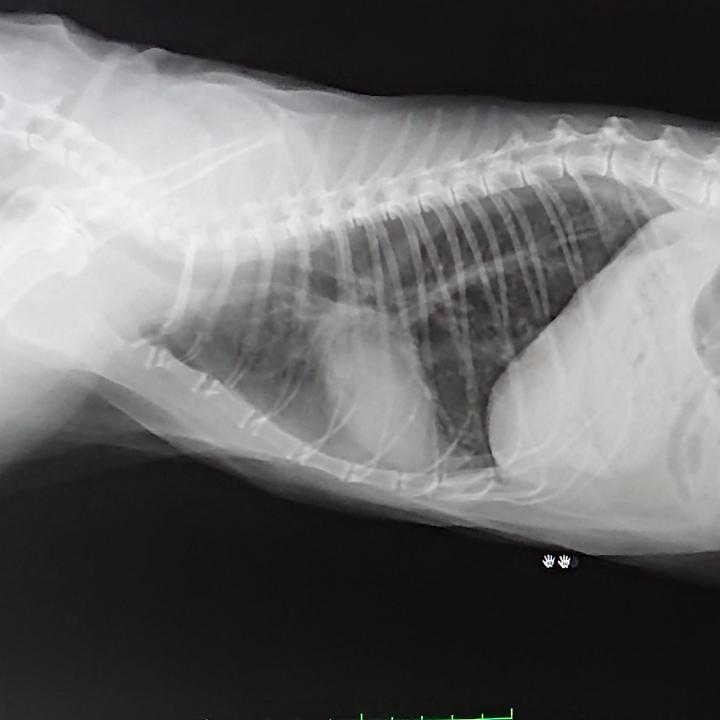

レントゲン、エコー、血液検査。

鼻がちょっと変な感じ。

3人の先生に診てもらっても、腫瘍らしきものもないし、鼻を抜けた喉や肺は綺麗だと言うし…

だけど、主治医は鼻水を採取するには、麻酔が必要で、あまり腎臓数値がよろしくないココには現実的ではない。